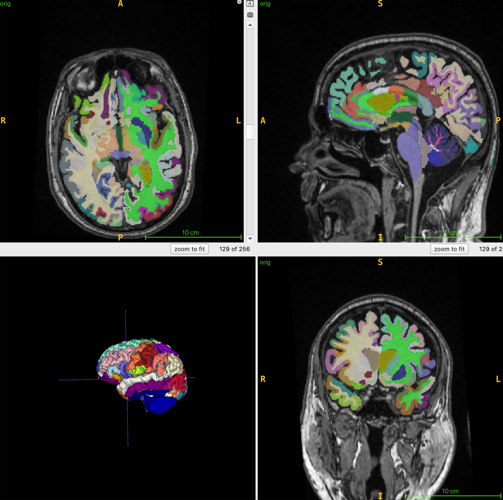

kAmw6 6IA=2:?65 E92E 3C2:? 286 :D E96 4@>AFE2E:@?2= 6DE:>2E:@? @7 49C@?@=@8:42= 286 7C@> 2 DECF4EFC2= |#x D42? @7 E96 3C2:?]k^Am

kAm%96 C6D62C49 E62> 4@>3:?65 |#x :>28:?8 H:E9 %`\H6:89E65 D6BF6?46D \ 2 E649?:BF6 E92E AC@5F46D :>286D H96C6 72E 2AA62CD 3C:89E 2?5 7=F:5 2AA62CD 52C<]k^Am

kAmsC] #2;: D2:5 E92E 2==@HD 7@C @AE:>2= :>28:?8 @7 >FD4=6[ 72E 2?5 3C2:? E:DDF6]k^Am

kAmp? k2 9C67lQ9EEADi^^E2=<6C]?6HD^a_ad^_h^_c^E:?J\42>6C2\2=@?8\H:E9\2:\42?\244FC2E6=J\AC65:4E\C:D<\@7\D64@?5\962CE\2EE24<^Q E2C86ElQ03=2?<Q C6=lQ?@C676CC6C ?@@A6?6CQm2CE:7:4:2= :?E6==:86?46k^2m WpxX 2=8@C:E9> H2D FD65 E@ BF2?E:7J E@E2= ?@C>2=:K65 >FD4=6 G@=F>6[ G:D46C2= 72E[ DF34FE2?6@FD 72E \ 72E F?56C E96 D<:? \ 2?5 3C2:? 286]k^Am